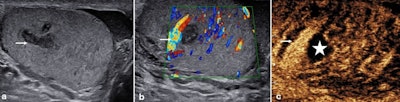

Epididymal abscess. A 56-year-old man with underlying diabetes mellitus presented with a left-sided scrotal mass and pain. On the B-mode ultrasound (a), a 20 x 22 mm mixed reflective mass was present in the epididymis (arrow). The color Doppler ultrasound (b) showed a lack of vascularity within the abnormality (arrow), with the contrast-enhanced ultrasound (c) showing absence of enhancement and vascularity centrally (star) and surrounding hyperemia (arrows). An epididymal abscess was present with reduced symptoms in an immuno-compromised diabetes mellitus patient.